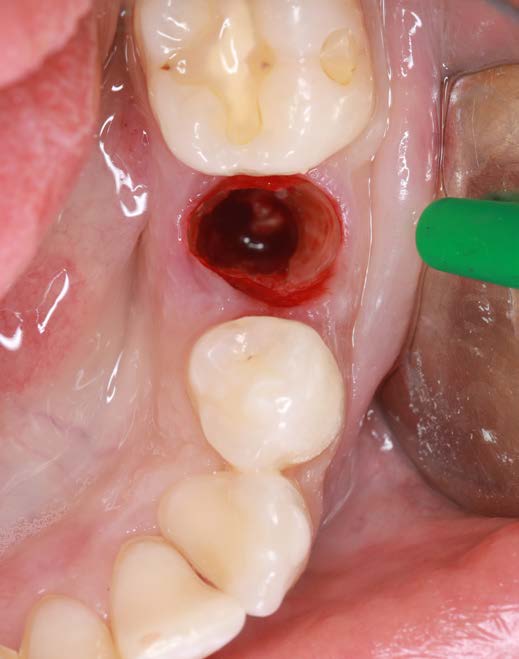

Figure 3: Condition after extraction and preservation of the buccal root portion |

A 26-year-old female patient was referred to my practice. Tooth 35 was deemed non-restorable. A CBCT scan showed the buccal bone plate was missing. Especially in aesthetic zones, we aim to reduce tissue collapse post-extraction (up to 50%). We considered various ridge preservation techniques to minimize this risk.

Surgical Approach

I chose the Socket Shield Technique, a minimally invasive method to reduce tissue shrinkage and achieve better long-term aesthetic outcomes. The technique requires healthy periodontal tissue and an intact root, both of which were present. The tooth is partially extracted, leaving the buccal root portion to support the soft tissue. This maintains the buccal periodontal attachment, allowing the tissue to behave as if the tooth were still in place. Hürzeler et al. introduced this technique in 2010 to reduce tissue shrinkage during immediate implantation.